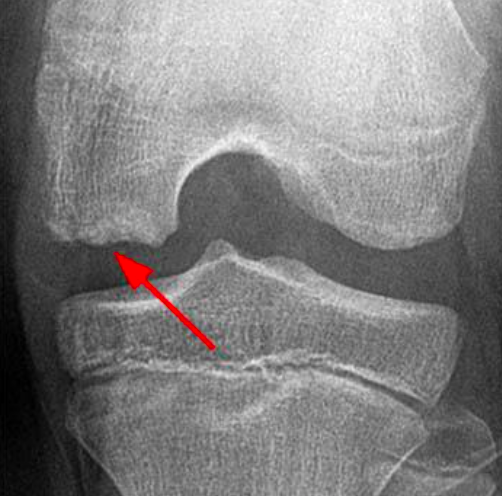

2. Osteochronditis Dissecans

Osteochronditis dissecans of the knee joint

(Image taken from Orthobullets.com)

• What is it? This affects the articular cartilage and sub-chondral bone, of primarily the knee joint. But it can also be found in the elbow (capitellum). In 50% of cases it occurs gradually. Average age of 13 years, with males 4 times more likely to sustain this injury compared to females. 97% are vitamin D deficient.

• Common Symptoms : Knee pain and effusion (swelling). Symptoms can be vague or mild. In sports involving repetitive arm and elbow movements (e.g. hurling), lateral elbow pain and swelling are common symptoms.

• Treatment : MRI imaging is required. Treatment may be surgical or non-surgical.